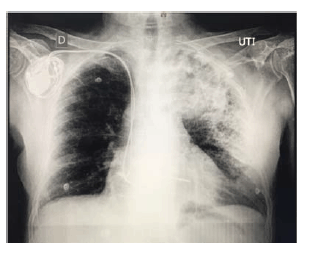

Considere um paciente de 66 anos de idade, com histórico de hipertensão arterial e diabetes controlados, além de ser cardiopata com marcapasso artificial. Relata calafrios com dois dias de evolução e tosse produtiva, além de estar taquipneico, com FR = 32 ipm, com PA = 110 mmHg x 82 mmHg; e com pulso = 126 bpm. Refere cansaço com dispneia. Tem nível de consciência preservado, com SatO2 = 89% (ar ambiente) e ureia = 58 mg/dL (VR = 5 mg/dL – 40 mg/dL). Apresenta o exame de raios X de tórax mostrado e nega internação ou uso de antibióticos no último ano.

Com relação a esse caso clínico e com base nos conhecimentos médicos correlatos, julgue os itens a seguir.